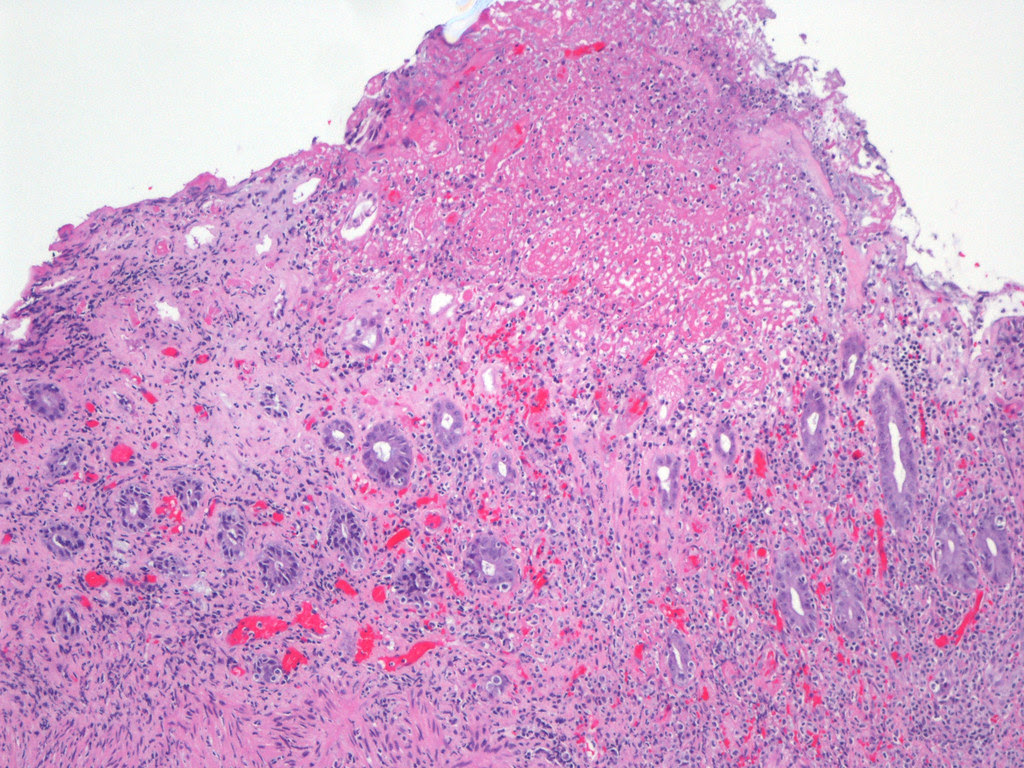

Herpes | the most comprehensive educational site. Additionally, it appears that the. From there, it tends to recur on the lower lip or face. To prevent a possible recurrence, use a sunblock that contains zinc oxide on. This gallery shows various herpes pictures, and also a couple of images of conditions that may mimic a herpes infection like chickenpox or canker sores. However, most people do not have any symptoms. Pictures of herpes reveal a range of symptoms. More information on the types of herpes is below. Sometimes, too, sores appear on the tongue or face. Copyright dr linda m stannard, university of cape town, south africa, 1995 (used with permsssion). Herpes is caused by two different viruses: Because children have no prior infection with any hsv type, they have no immune defence against the virus. You may have an outbreak when you're sick, after you've been out in the sun, or when you're stressed out or tired.

How do you contract hsv 1? Sometimes, too, sores appear on the tongue or face. These two viruses have distinctly different dna, and both. You may have an outbreak when you're sick, after you've been out in the sun, or when you're stressed out or tired. More information on the types of herpes is below. This gallery shows various herpes pictures, and also a couple of images of conditions that may mimic a herpes infection like chickenpox or canker sores. We'll explain how herpes simplex is transmitted, symptoms, and treatment options. Copyright dr linda m stannard, university of cape town, south africa, 1995 (used with permsssion).